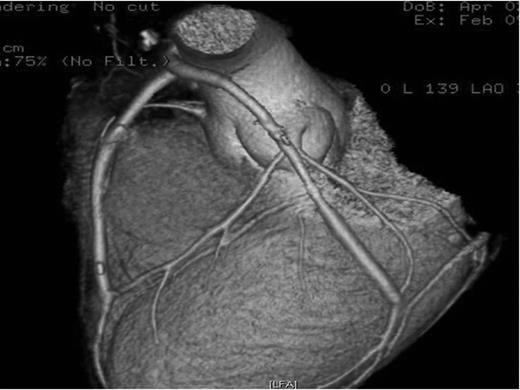

The patient underwent emergent coronary revascularization with saphenous vein grafts to the first obtuse marginal and the left anterior descending artery (LAD). His postoperative course was uneventful and the patient was discharged home 7 days later. Control CT coronary angiography was performed 2 months later revealing patent aorto-coronary grafts (Fig. 3).

CT coronary angiography reconstruction showing patent grafts to the LAD and obtuse marginal arteries.